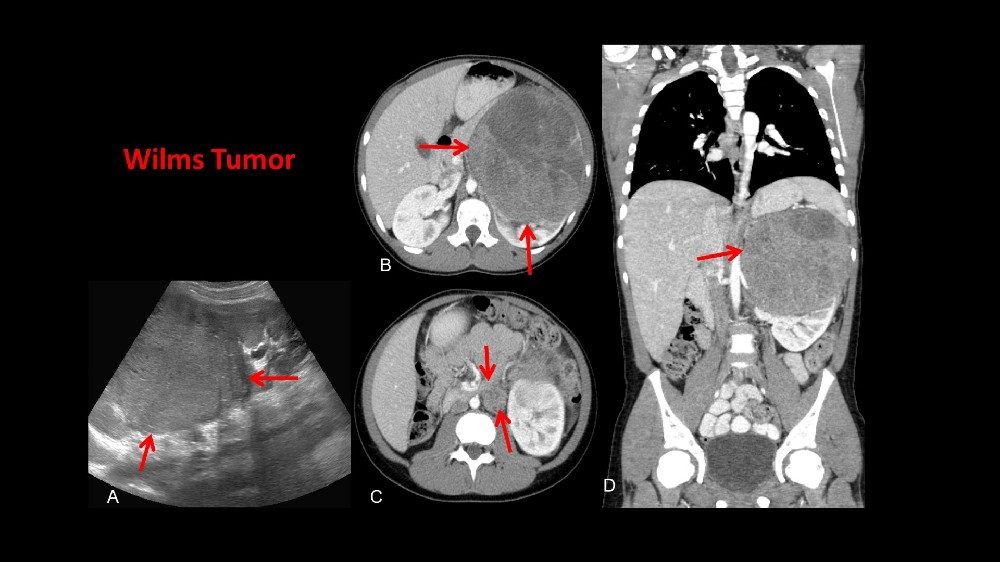

什麼是Wilms腫瘤(腎母細胞瘤)?

Wilms 腫瘤(腎母細胞瘤) Wilms 腫瘤 (腎母细胞瘤) 是一種罕見但可治療的兒童腎臟癌症,主要影響 3-4 歲的兒童,但偶爾也會診斷出年紀較大的兒童,成人則很少見。了解 Wilms 腫瘤 (腎母细胞瘤) 首先要知道它的生理基礎,即未成熟腎細胞的異常生長。